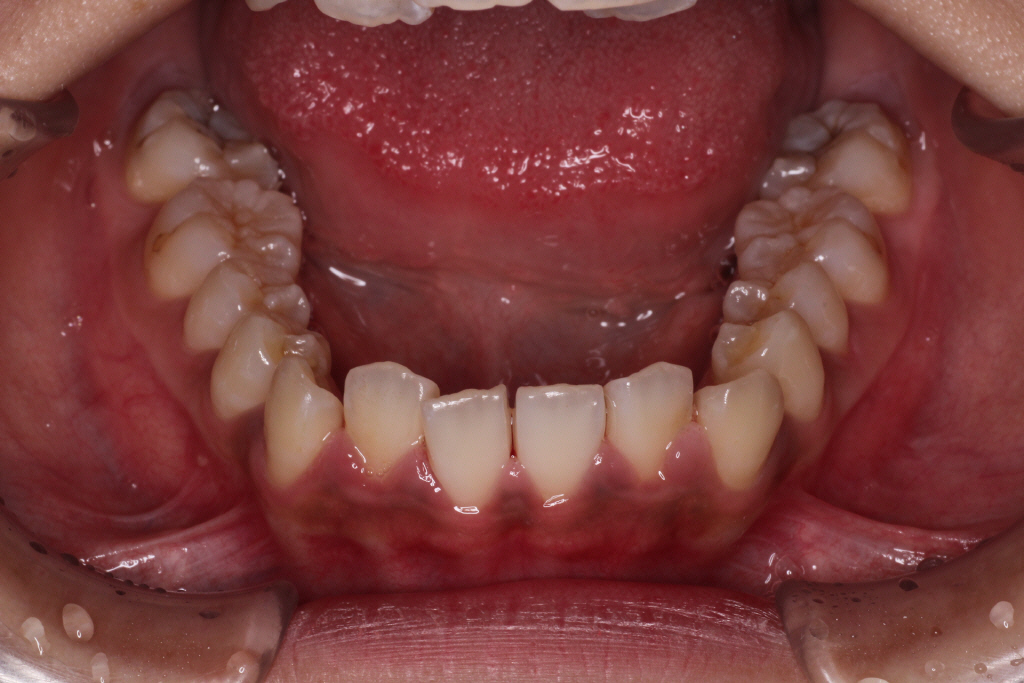

51枚中27枚目くらいでマウスピースが合わなくなった9ヶ月後のお口の中の状態です。

患者さんの左上の1番目と3番目の間に隙間ができてきて、2番目の歯が少し見えるようになりました。

まだまだ並ばせていかないといけないので、リファイメント1回目(マウスピースの作り直し)を行いました。